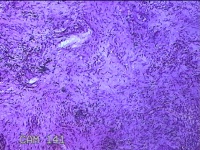

舌头肿物

性别

女

年龄

25岁

临床诊断

一般病史

无

标本名称

大体所见

灰白粉红色肿物0.7x0.5x0.2cm一个,表面光滑。

图1

纤维性息肉